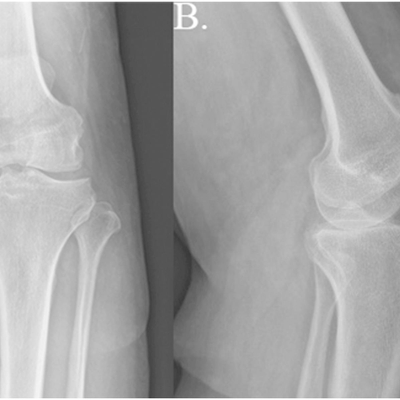

Click on an image below to view more info.